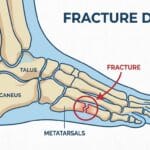

Traumatismes fréquents : entorses, foulures et micro-fractures méconnues

- Une entorse mal soignée peut créer une instabilité chronique.

- Certaines micro-fractures passent inaperçues à la radiographie initiale.

- La compensation musculaire entraîne des douleurs projetées vers le haut.

⚠️ Exemple : une entorse externe du ligament latéral peut provoquer une inflammation du tendon péronier latéral, douloureuse jusqu’au mollet.

Radiographie de la cheville et du tibia

- Elle permet d’exclure une fracture, un arrachement osseux ou une arthrose articulaire.